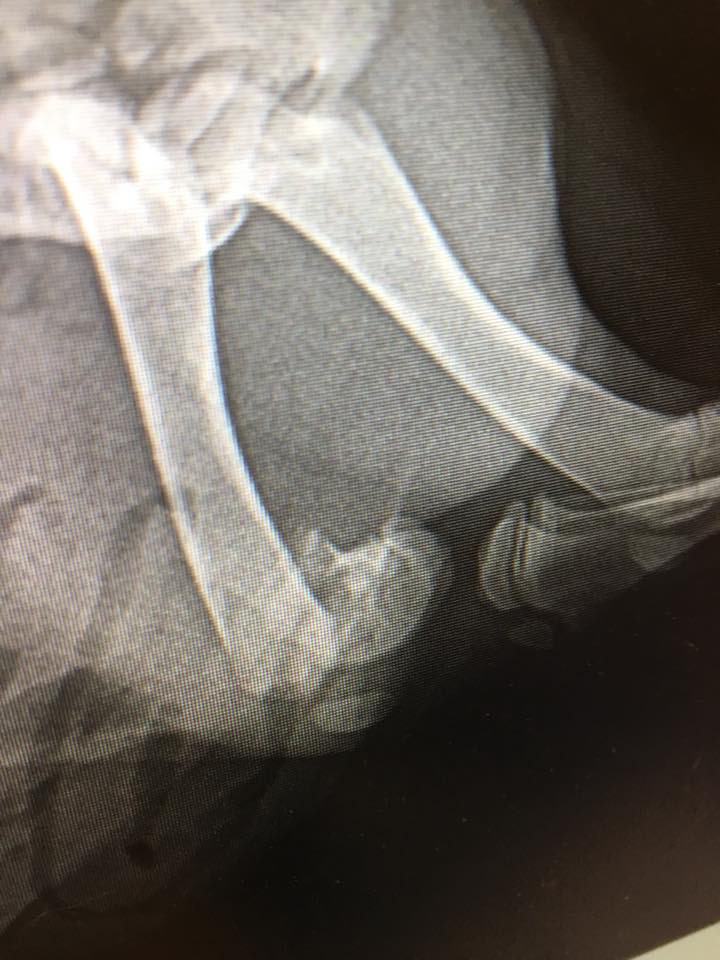

Olli (BLK / WHITE CHIHUAHUA PUPPY)

Latest Updates

Help us, help him!

Your donation will help Olli (BLK / WHITE CHIHUAHUA PUPPY) recover.